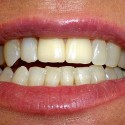

Foto 2: Risultato finale: le due corone in occlusione.

Previa rimozione dell’impianto fratturato, furono inseriti due nuovi impianti endossei e dopo il periodo di osteointegrazione furono applicate due corone in porcellana.